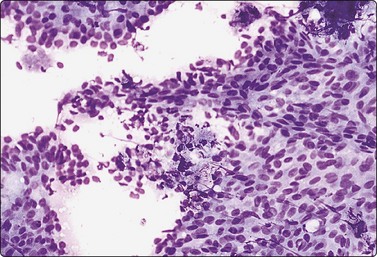

image image

Fig. 7.15 Regenerative epithelial atypia in mastitis

(A) Atypical, reactive/regenerating epithelial cells with a background of histiocytes, inflammatory cells and debris (MGG, HP); (B) Corresponding tissue section (H&E, IP).